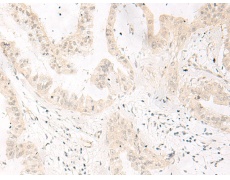

IHC positive control: |

Human liver cancer |

IHC Recommend dilution: |

10-50 |